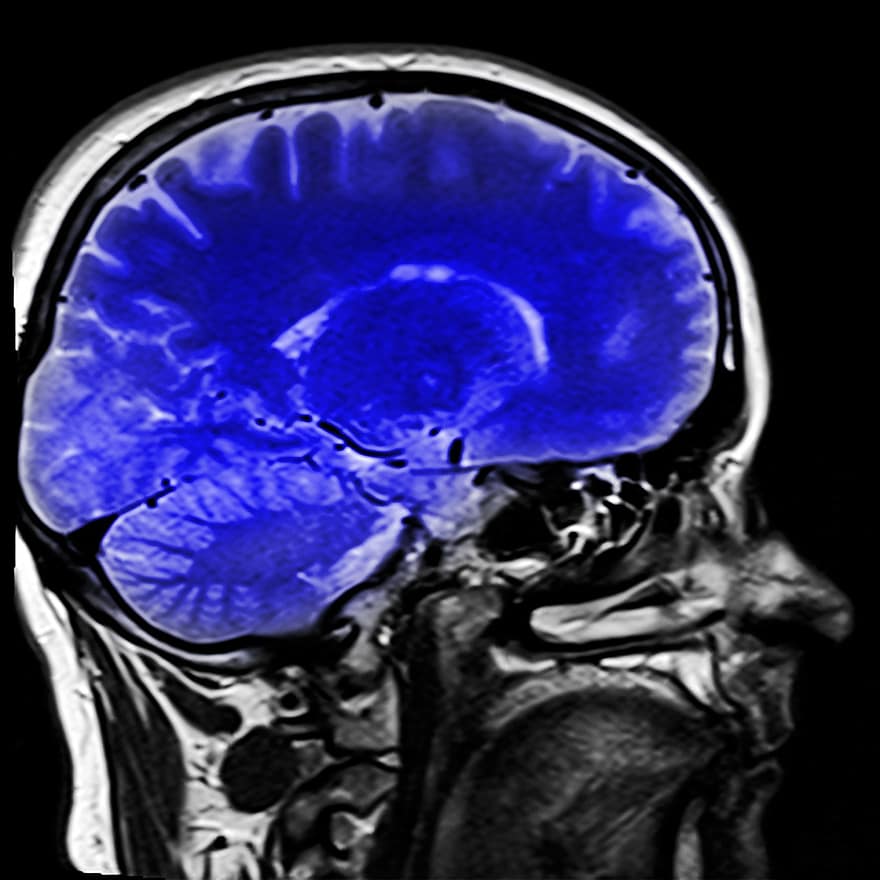

head-magnetic-resonance-imaging-mrt-x-ray.jpg

我们的大脑是由坚硬的颅骨保护的脆弱器官,但有时也需要额外的保护